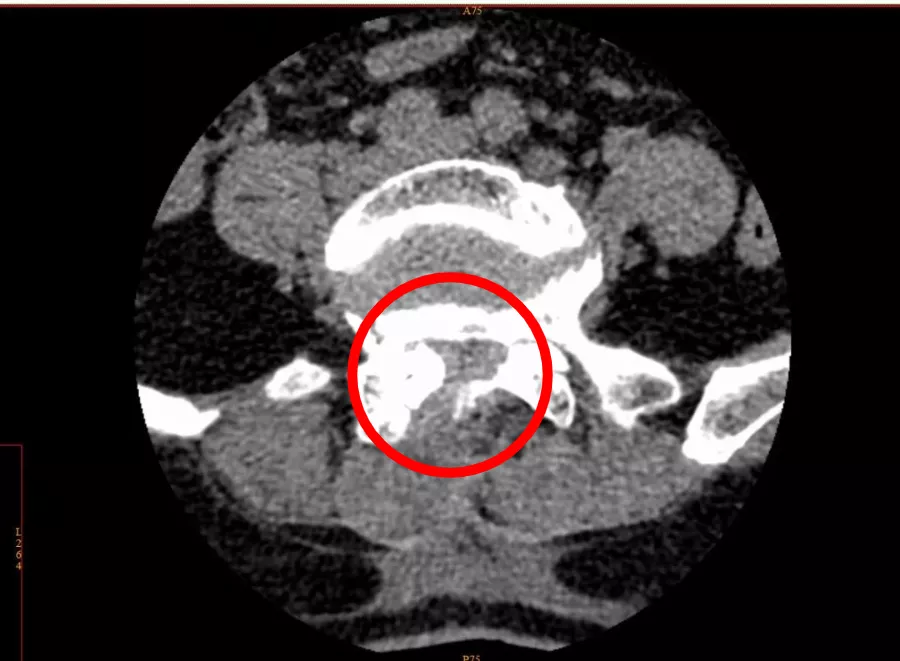

术后,腰椎管狭窄改善

除手术治疗外,疼痛科团队还在术前、术后辅以壮医药熨、壮医敷贴等疗法,以促进其局部血液循环,在消肿、抗炎 、镇痛的同时,巩固手术疗效。

12月28日,李女士康复出院。